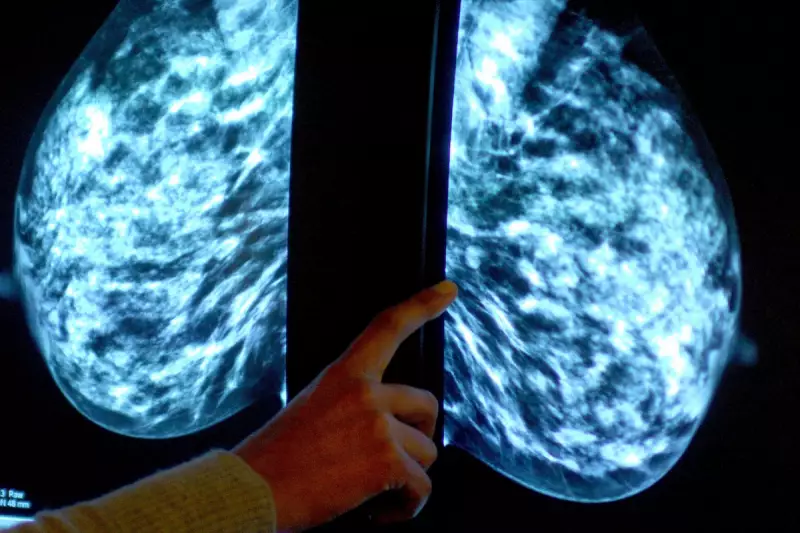

In a medical breakthrough that could transform preventive healthcare for women, a major new study has revealed that routine mammograms might do more than just detect breast cancer—they could also predict a patient's risk of having a heart attack.

The pioneering research, presented this week at the Radiological Society of North America's (RSNA) annual conference, suggests that breast X-rays can identify early signs of arterial calcification in the breasts. This condition is a known marker for calcium buildup in arteries, a primary cause of cardiovascular disease.

The research focuses on breast arterial calcification (BAC), which appears as white spots on mammogram images. While these calcifications are different from those associated with cancer, they indicate the presence of calcium in the blood vessels of the breast.

This finding is significant because calcium buildup in arteries is a known precursor to atherosclerosis—the hardening and narrowing of arteries that can lead to heart attacks and strokes.